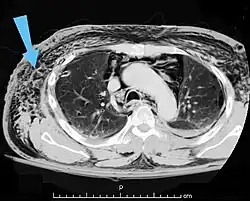

Scanner abdominal (rayons X) d'un patient présentant des emphysèmes sous-cutanés (fléchés). | |

Les cas importants d'emphysème sous-cutané sont faciles à diagnostiquer en raison des signes caractéristiques de l'affection. Dans certains cas, les signes sont subtils, ce qui rend le diagnostic plus difficile. L'imagerie médicale est utilisée pour diagnostiquer la maladie ou confirmer un diagnostic établi à l'aide de signes cliniques. Sur une radiographie du thorax, l'emphysème sous-cutané peut être vu comme des stries radiotransparentes dans le modèle attendu du groupe de muscles principaux du pectoral. L'air présent dans les tissus sous-cutanés peut interférer avec la radiographie du thorax, ce qui peut masquer des affections graves comme le pneumothorax. Elle peut également réduire l'efficacité de l'échographie thoracique. D'autre part, comme l'emphysème sous-cutané peut être visible sur les radiographies du thorax avant un pneumothorax, sa présence peut être utilisée pour déduire celle de cette dernière lésion. L'emphysème sous-cutané peut également être observé sur les scanners, les poches d'air apparaissant comme des zones sombres. Le scanner est si sensible qu'il permet généralement de trouver l'endroit exact d'où l'air pénètre dans les tissus mous. En 1994, M. T. Macklin et C. C. Macklin ont publié d'autres aperçus sur la physiopathologie du syndrome de Macklin spontané survenant à la suite d'une grave crise d'asthme. La présence d'un emphysème sous-cutané chez une personne qui semble très malade et fébrile après une crise de vomissements suivie d'une douleur thoracique gauche est très évocatrice du diagnostic du syndrome de Boerhaave, qui est une urgence vitale causée par une rupture de l'œsophage distal. L'emphysème sous-cutané peut être une complication de l'insufflation de CO2 avec la chirurgie laparoscopique. Une augmentation soudaine du CO2 en fin de marée après la hausse initiale qui se produit avec l'insufflation (les 15-30 premières minutes) devrait faire suspecter un emphysème sous-cutané. Il est à noter que l'oxymétrie de pouls et la pression des voies aériennes ne varient pas dans l'emphysème sous-cutané, contrairement à l'intubation endobronchique, au capnothorax, au pneumothorax ou à l'embolie au CO2.